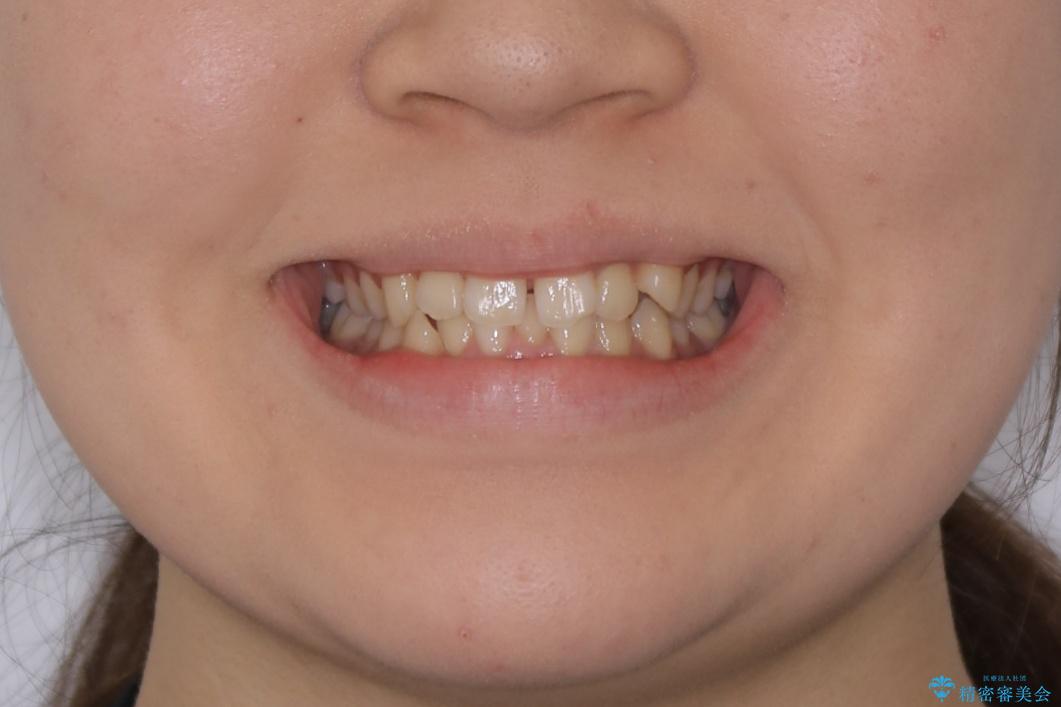

- 上の前歯のすきっ歯と下の前歯のガタつきを主訴にご来院されました。

噛み合わせの改善も同時に進めつつ、主訴の部分も効率的に治していくためマウスピース装置でゴムかけを行いながら治療を進めていきました。

正中離開(すきっ歯)

真ん中の歯が左右に開いてしまい隙間ができてしまう状態を「正中離開」といい、俗にすきっ歯と呼ばれています。

隙間を埋めていく方向に歯を移動させることで改善していくケースが多く、比較的治りやすい不正咬合のひとつとされています。

しかしながら、歯が捻じれていたり、噛み合う歯との位置関係によっては治療が難しくなる場合があります。